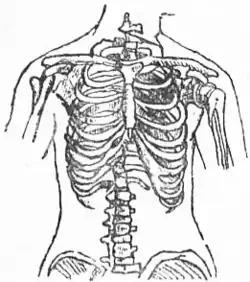

В середине XIX столетия корсеты стали предметом резкой критики со стороны медиков. Врачи настаивали на негативном влиянии корсета на женский организм — медицинская критика фактически вытеснила отрицательную оценку этого вида одежды моралистами[2].

Ношение корсета представляет собой один из вреднейших и опаснейших для здоровья обычаев. Стягивание грудной клетки, особенно нижней, наиболее податливой её области, влечёт за собой нарушение правильной деятельности органов грудной и брюшной полостей. Вследствие сжатия нижних долей лёгких кровь недостаточно окисляется и в результате получается малокровие и неправильная деятельность сердца. Вместе с тем сдавливаются и смещаются печень, желудок и кишечный канал, причём первая нередко претерпевает местами рубцовое перерождение, а другие органы, оттеснённые вниз, давят на органы тазовой полости и на крупные брюшные сосуды. Усиленные движения (танцы, езда на велосипеде) при туго стянутом корсете нередко бывали причиной внезапной смерти. В громадном большинстве случаев тугое стягивание корсета служит причиной развития самых разнообразных женских страданий, а, сдавливая соски и сами грудные железы, лишали женщин возможности кормить своих детей грудью.Энциклопедический словарь Брокгауза и Ефрона / под ред. проф. И. Е. Андреевского. Т. 16. — СПб., 1895.

Корсеты начинали носить в возрасте 4—5 лет, что приводило к систематическим искажениям костной ткани: ребра и внутренние органы развивались с нарушениями и приобретали деформации. В 1903 году парижский врач Жозефина Гош-Саро предложила разделить корсет на две составляющих: верхнюю — для поддержки груди, и нижнюю — пояс для чулок. Это деление было положено в основу бельевой схемы всего XX века и, фактически, сохраняется в женской нижней одежде до сих пор. Несмотря на критику, корсет оставался центральным элементом одежды на протяжении нескольких столетий.